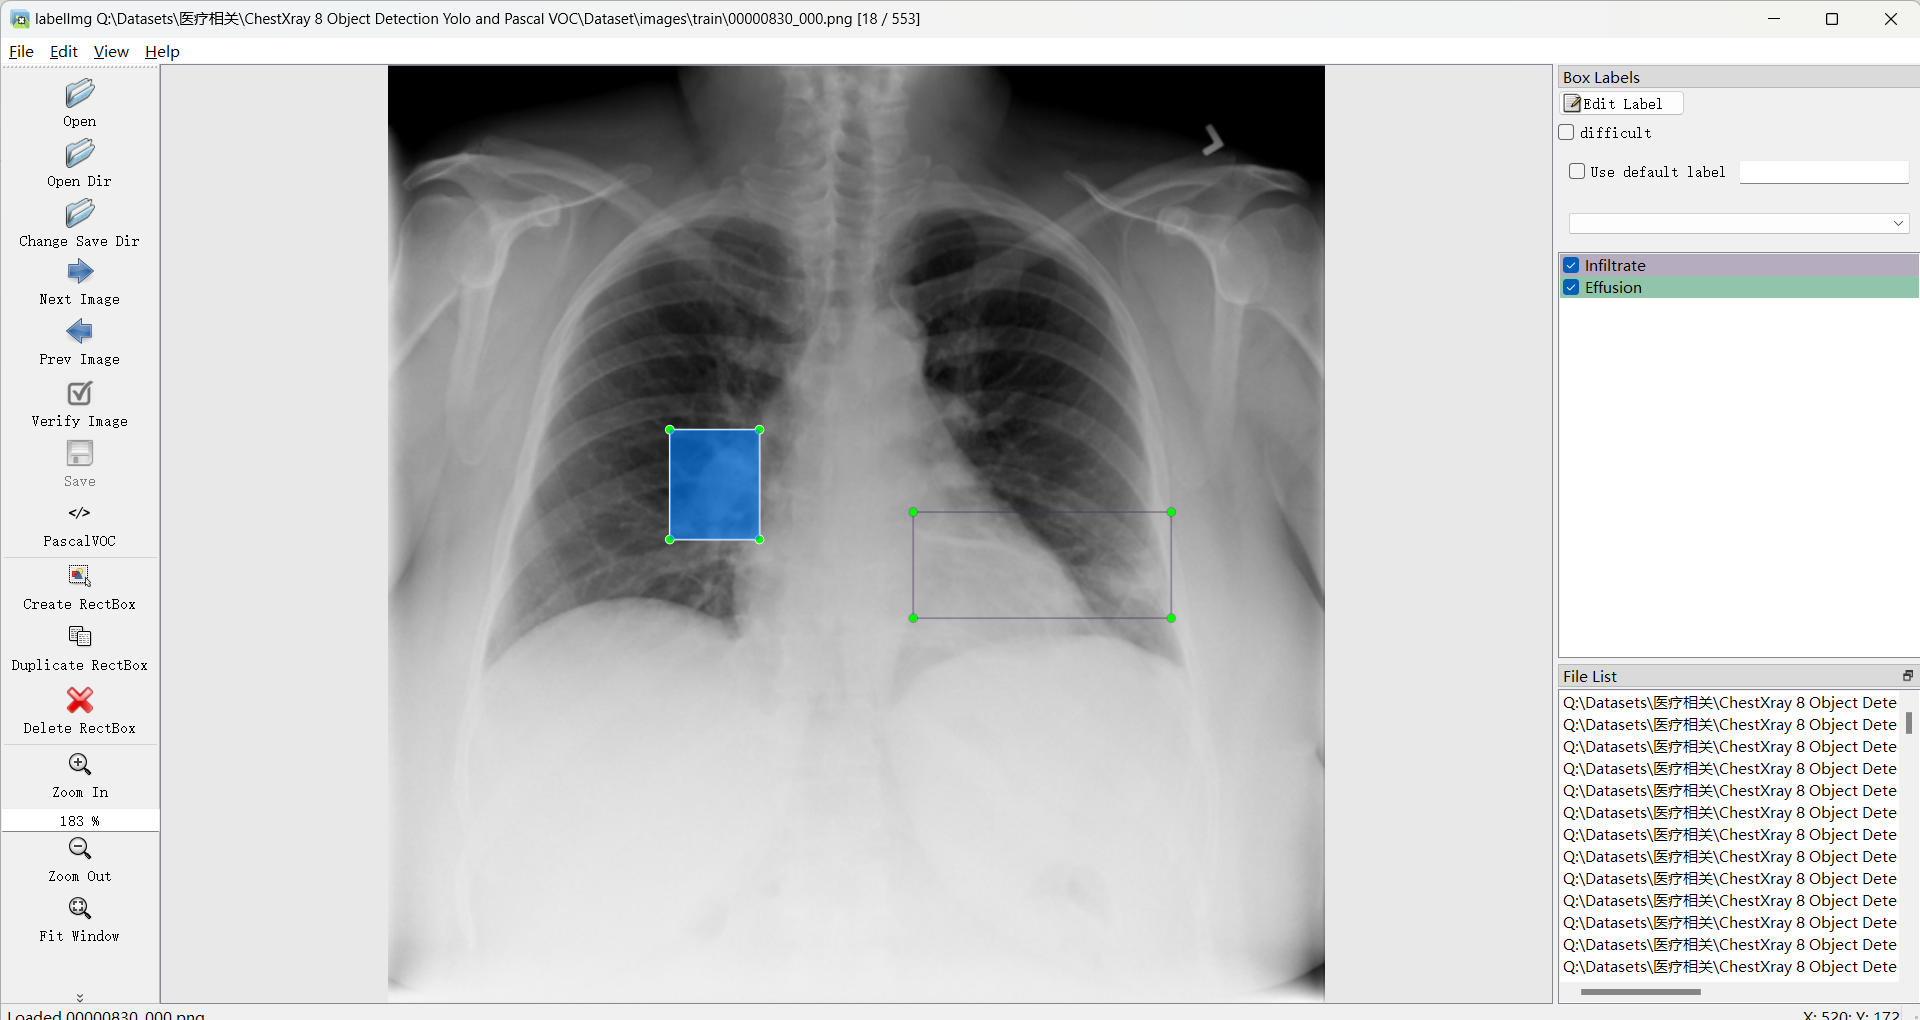

标注类别名称: Infiltrate:浸润影;Atelectasis:肺不张;Cardiomegaly:心脏肥大;Nodule:结节;Effusion:积液(胸腔积液)

使用标注工具:labelImg

标注规则:对类别进行画水平矩形框

标注示例: